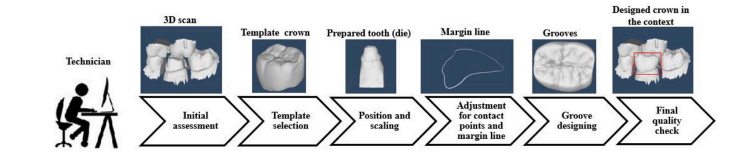

牙科实验室每年都要负责使用计算机辅助设计(CAD)软件,根据每位患者独特的牙齿形态和具体特征,设计数百个定制牙冠。这个过程始于牙医对受损牙齿进行预备,为安装牙冠奠定稳固的基础。然后,使用口腔内扫描仪获取预备牙齿及其相邻牙齿的三维数字模型,为定制牙冠的设计提供必要的背景信息。 一位牙科技师会使用配备了牙科专用工具的CAD系统,精心设计牙冠。这一步骤包括从数字库中选择一个标准的牙齿模板,并通过仔细的缩放和定位对其进行修改,以满足功能和美观的要求。整个手动设计过程,包括对接触点和边缘线的关键调整,都在流程图(图1)中有所展示。这些调整确保牙冠与牙齿预备体完美贴合,并在预备体的边缘线处牢固密封。还会进行进一步的精细调整,以确保与相邻牙齿正确接触。流程图(图1)展示了每年为满足每位患者的需求而手动设计数百个牙冠时所涉及的详细调整和定制过程。 尽管CAD系统提供了高精度,但手动设计过程既耗时又容易出现人为错误。每个牙冠的设计可能需要一个多小时,而且要在不同设计之间保持一致性颇具挑战性。因此,需要一种基于人工智能的自动化解决方案,以提高牙冠设计的准确性、效率和一致性。 为了应对这些挑战,新兴的人工智能(AI)和深度学习技术提供了很有前景的解决方案。最近的研究表明,人工智能有潜力通过模糊逻辑和卷积网络等技术提高诊断精度(段等人,2018年;拉吉和米蒂利,2021年;吴等人,2017年)。在图像分割方面也取得了重大进展,采用了双重注意力模块、边界感知Transformer、基于生成对抗网络(GAN)的模型以及域适应方法,以提高医学应用中的分割质量和边界检测能力(吴等人,2020年;王等人,2023年;雷等人,2021年;潘迪等人,2020年;丁等人,2021年;田等人,2021b)。在三维牙科重建领域,一些特定研究推动了合成图像重建和修复性修复的发展,通过创新的基于GAN和Transformer的模型,专注于详细的牙冠形态、牙龈边缘线生成和咬合面重建(田等人,2022a;丁等人,2023年;田等人,2021a,2022b;阿尔谢赫里等人,2024年)。总体而言,这些人工智能方面的创新满足了自动化、准确性和效率方面的关键需求,尽管在计算需求、数据质量和通用性方面仍然存在局限性。 在这些进展的基础上,最近在牙冠设计自动化方面的努力集中在通过将三维牙科扫描转换为二维深度图像来简化扫描过程(黄等人,2018年;袁等人,2020年)。使用了pix2pix技术(伊索拉等人,2017年)来生成牙冠图像。虽然这种方法可以从单个视角可视化牙冠的咬合面,但它本质上忽略了对于合适牙冠至关重要的侧面部分。侧面对于确保牙冠牢固地贴合在牙齿周围并与相邻牙齿正确对齐起着关键作用。此外,侧面边缘对于保持正确的咬合对齐(咬合关系)以及防止牙菌斑堆积或牙龈刺激等问题至关重要。未能捕捉到这些方面会影响牙冠的稳定性、与相邻牙齿的美观融合以及其整体使用寿命。从三维到二维的转换会导致大量空间信息的丢失,尤其是在牙齿边缘线周围。而且,这些二维方法不能直接生成完整的牙齿表面,使得从咬合面视图获取详细的侧面变得并非易事。针对这些局限性,点云已成为一种更优的替代方案。与二维成像不同,点云可以忠实地表示任何三维形状,捕捉整体形状和复杂的细节。在这种背景下,莱萨德等人(2022年)引入了一种基于点云的方法,该方法首先从给定的颌骨中随机移除一颗牙齿。随后,网络使用一个生成特征点的多尺度网络来估计缺失的牙齿。然而,这种方法没有模拟更现实的场景,即为准预备好的牙齿生成牙冠。因此,他们的预测在定位上会出现不准确的情况。此外,由于该方法生成的是点云而不是网格,它对生成形状的光滑度控制有限。为此,后续的一项研究(朱等人,2022年)开发了一种基于Transformer的网络,旨在为缺失的牙齿创建牙冠的表面网格。他们的方法涉及两个不同的网络:一个生成点云,另一个基于第一个网络生成的牙冠点来重建网格。然而,该方法仅依赖于点距离损失度量,如倒角距离(CD),来优化点云。它缺乏一个特定的损失函数来管理网格重建过程,这极大地限制了其精确控制最终网格输出质量和准确性的能力。 在之前的工作中,我们团队发表了一项关于牙齿网格补全(DMC)模型的开创性研究(侯赛尼马内什等人,2023b),提出了一种端到端的深度学习模型,旨在从输入的点云直接生成牙冠网格。该模型利用基于Transformer的架构和自注意力机制,从牙齿预备体和周围牙齿的三维扫描中预测特征。然后,利用这些特征将二维固定网格变形为三维点云。随后,一个可微的点到网格模块预测指标网格,这有助于生成网格。该模型的训练结合了点云的倒角距离损失和网格的均方误差(MSE),旨在加强对牙冠特征的学习。尽管取得了这些进展,但提高输出点云的分辨率对于Transformer来说仍是一个挑战,难以生成无噪声的结果。虽然引入均方误差损失和倒角距离损失一起可以改善点云的分布,但该方法仍然难以生成高分辨率的点云。这一限制阻碍了它预测高质量网格的潜力。此外,它没有有效地解决在预备牙齿的边缘线位置准确贴合牙冠这一关键问题。另一项关于为预备牙齿生成牙冠的研究通过整合预备牙齿的边缘线数据,提高了关键边缘线处的准确性(侯赛尼马内什等人,2023a)。这种方法显著提高了边缘线区域的精度。然而,他们表示为点云的牙冠需要额外的步骤才能转换为网格。 为了解决这些问题,我们引入了一种新的端到端网络,旨在为所有牙齿位置直接生成高质量的牙冠。我们的模型利用Transformer编码器 - 解码器架构,结合自注意力机制、自适应查询生成和去噪任务策略,来处理来自牙齿预备体和相邻牙齿三维扫描的点。这种方法使我们的网络能够动态地预测一组准确概括牙冠几何形状的特征。然后,这些特征通过一个全连接层来重建牙冠的点云,Transformer的先进机制确保了高分辨率且无噪声点云的预测。这些点的法向量通过一个简单的多层感知器(MLP)得出。集成到我们网络中的一个可微点到网格模块有助于三维表面重建。整个过程由对比学习倒角损失(InfoCD)(林等人,2023b)监督,在通过互信息估计捕捉表面相似性的同时,优化预测和真实值之间的点分布。此外,边缘线损失确保预测点在边缘线周围的准确对齐,这对于牙冠在预备牙齿上的正确贴合至关重要。从目标牙冠网格计算出的指标网格函数进一步指导重建的准确性。 大量的实验验证了我们方法的有效性及其创新贡献,展示了在牙冠生成方面的进展。综上所述,本文的贡献如下: 1. 提出了一种用于为所有牙齿位置生成个性化牙冠的自动化端到端网络。 2. 开发了一种完全可微的点到网格架构,通过基于Transformer的补全机制直接从三维点云生成牙齿网格。 3. 开发了旨在改善牙冠对齐和准确性的定制损失函数,包括用于精确定位的边缘线损失和用于优化表面匹配的先进对比学习倒角损失(InfoCD)。这些创新提高了牙冠生成过程的整体可靠性和准确性。

Fig. 1. Flowchart of manually designing a dental crown by a technician. This process usually takes more than 1 h.

图1:技术人员手动设计牙冠的流程图。这一过程通常耗时超过1小时